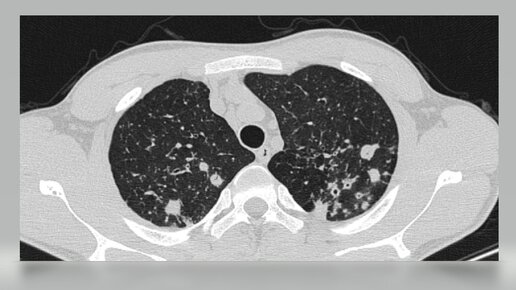

С пациентом, у которого на рентгенограмме органов грудной клетки обнаружены изменения в легких, может столкнуться врач любой специальности. В данной статье хотелось бы рассказать какие клинические формы туберкулеза легких встречаются в практике фтизиатра, на что необходимо обращать внимание, чтобы не пропустить пациента с туберкулезом легких. Классификация туберкулёза Итак, по клинической классификации, принятой в Российской Федерации, туберкулез можно разделить на две большие группы: первичный и вторичный туберкулез...